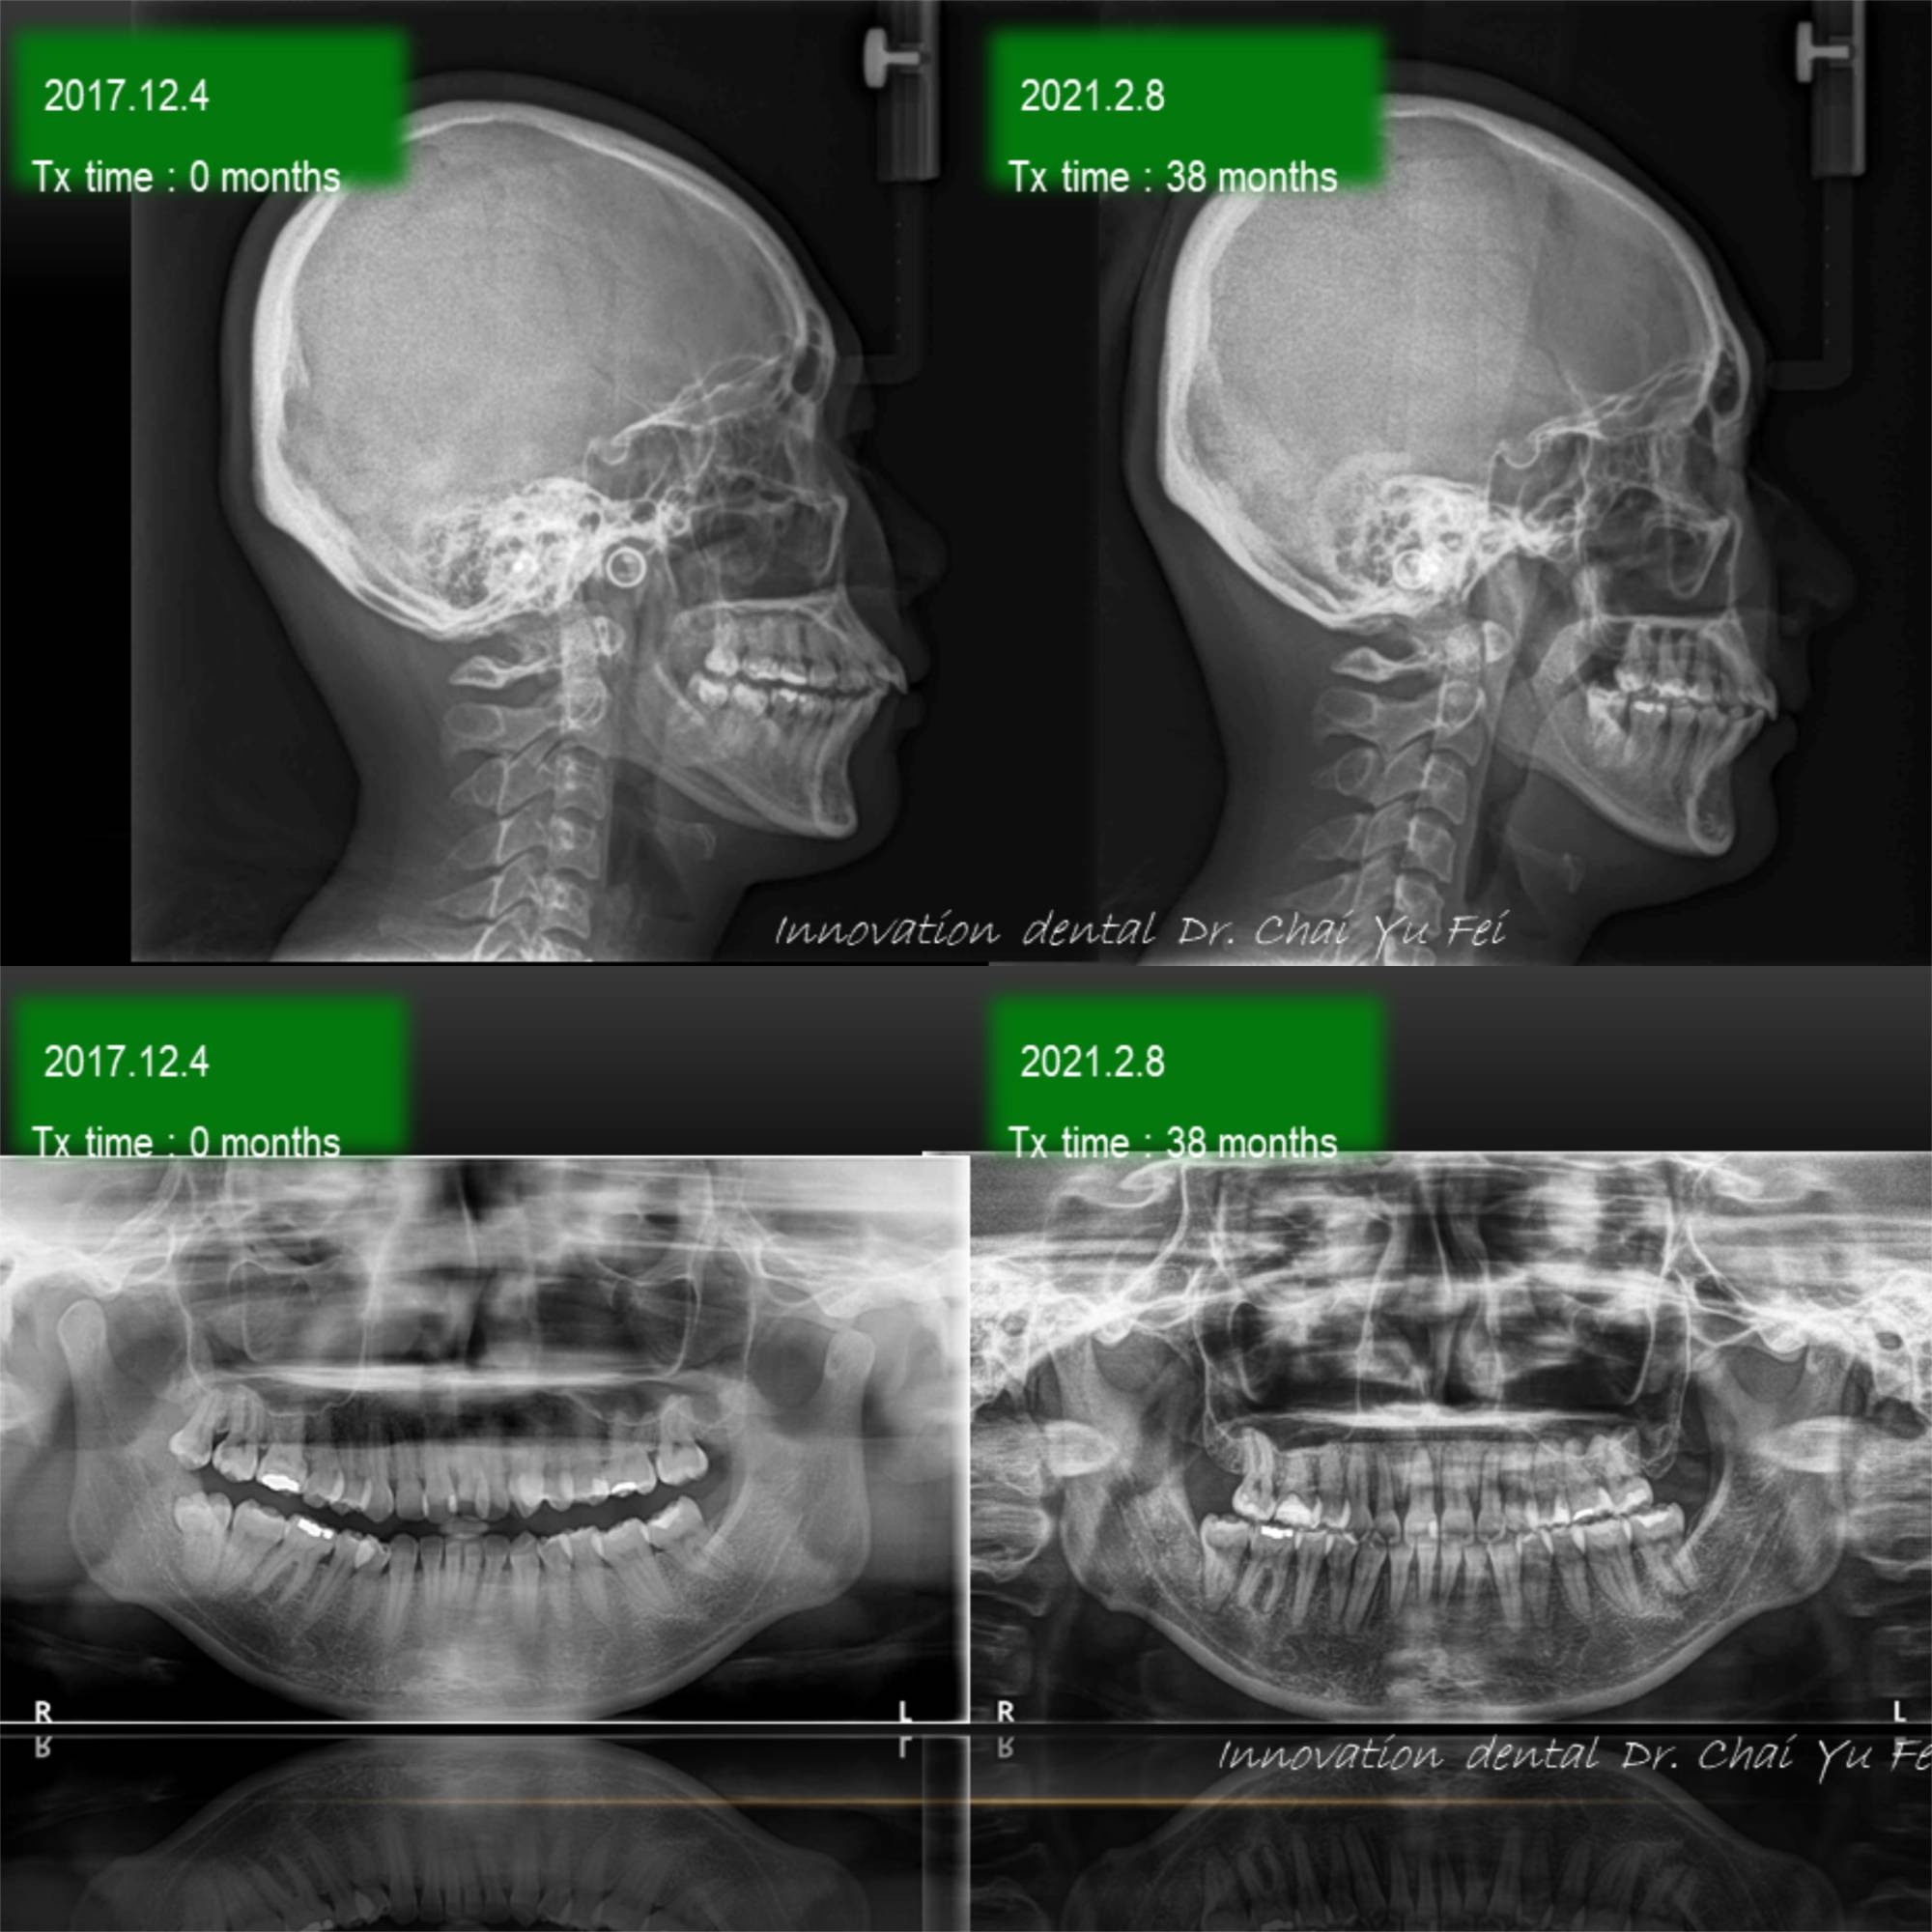

以這次黃小姐的案例來說,可以從照片中看到,由於上顎齒列狹窄,前牙角度往外傾斜,進而造成唇形前突不理想。

為了避免過度治療而傷害了原本可以恢復青春美麗的外觀,翟醫師決定採取上顎拔2顆小臼齒,下顎不要拔牙,在保留最多自然牙的情況下,改善下顎角度達到最美麗的外觀輪廓跟理想的咬合。

拔牙矯正前後變化,改善嘴型前突

看到這樣的治療結果,相信您應該對拔牙沒有那麼擔心了,不論是拔4顆或是拔2顆牙齒,我們無非都是為了讓出更多空間,來把齒列調整整齊,選擇拔牙的牙位通常也是重複性高的小臼齒,或是有病灶的牙齒,具有重要功能及不可取代性的牙齒我們不會隨便拔除,即使要犧牲牙齒,我們設計的治療計畫也會將犧牲降到最小,而且完全不影響功能以及外觀。治療完成後,一樣有好的微笑曲線跟理想穩定的咬合。

このように、矯正治療では歯を抜かざるを得ないことが多いのです,歯が出ているため、普段から口が閉めにくい状態です,無理に閉じようとすると、口元が緊張するため長時間閉じることができませんでした.この理由で,上顎の第一小臼歯を抜歯し、叢生(そうせい)の改善と共に口唇(こうしん)の突出(とっしゅつ)感の改善を図ることにしました。

抜歯矯正治療によって、治療後では前歯の傾斜と前突が改善されたため、

上下の唇を無理やり閉じる必要がなくなりオトガイに固有の自然なカーブが現れています。